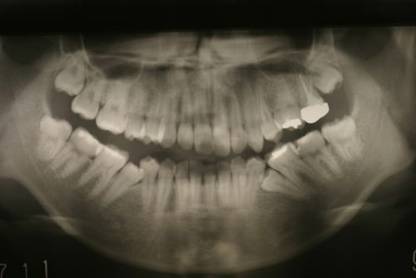

インビザGOによる矯正症例1 16歳男性

|

マウスピース矯正開始前。右上犬歯が内側にありました